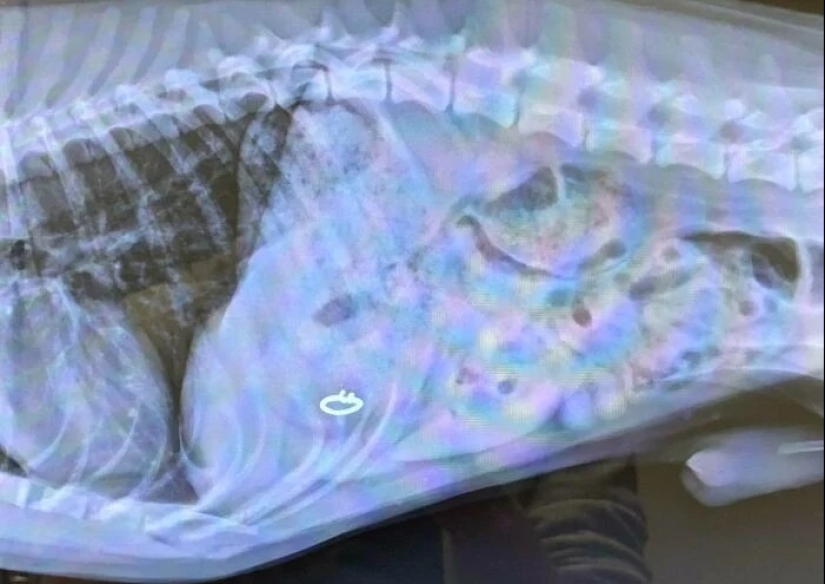

"Mi esposa perdió su anillo de bodas"